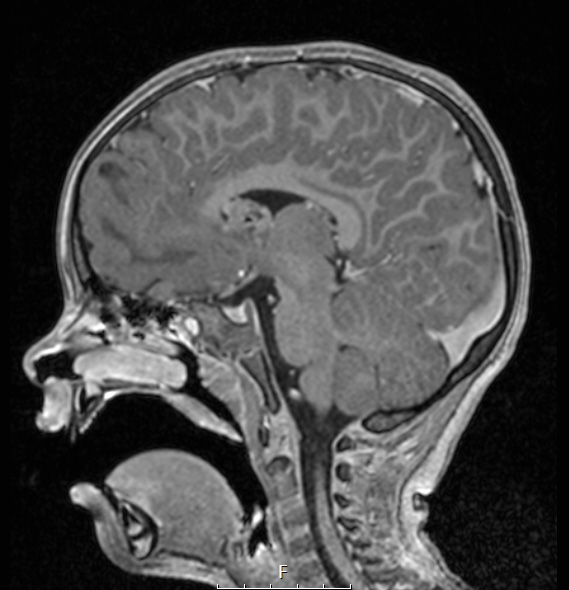

16A3,4 Neither the tuber nor SEGA enhance on this T1-weighted with contrast, sagittal (16A3) and axial (16A4) scans.